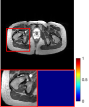

Figure 5 provides the qualitative comparison of the various methods on the four datasets at a scale of 4. The top, second, third, and bottom rows are the SR results under the FastMRI, clinical brain, clinical tumor and clinical pelvic datasets, respectively. The red boxes indicate the zoom-in region of complicated anatomical structures along with their corresponding error maps. Note that the brighter textures in the error maps, the lower the quality of the reconstructed images. As can be seen, compared to methods based on Transformers and CNNs, diffusion-based methods like DisC-Diff and DiffMSR (Ours) are capable of reconstructing high-realistic images with promising reconstruction metric scores (PSNR and SSIM). Nevertheless, while DisC-Diff can reconstruct high-precision MR images, it does not preserve the structure present in the original HR images, introducing some additional information that can affect medical diagnosis. In contrast, our method combines DM and PLWformer, which can preserve the original image’s structure while restoring high-frequency information.

In this section, we present more visual qualitative comparisons. Figures 8, 9, 10, and 11 show the reconstruction results of each method in FastMRI, clinical brain, clinical tumor, and clinical pelvic, respectively. As can be seen, although DisC-Diff can reconstruct MR images with high-frequency information, it fails to preserve the structure and content of the original Target HR image effectively, resulting in image distortion. In contrast, our proposed DiffMSR can restore high-frequency information while preserving the structure of the original HR image, indicating the effectiveness of the joint use of DM and PLWformer.